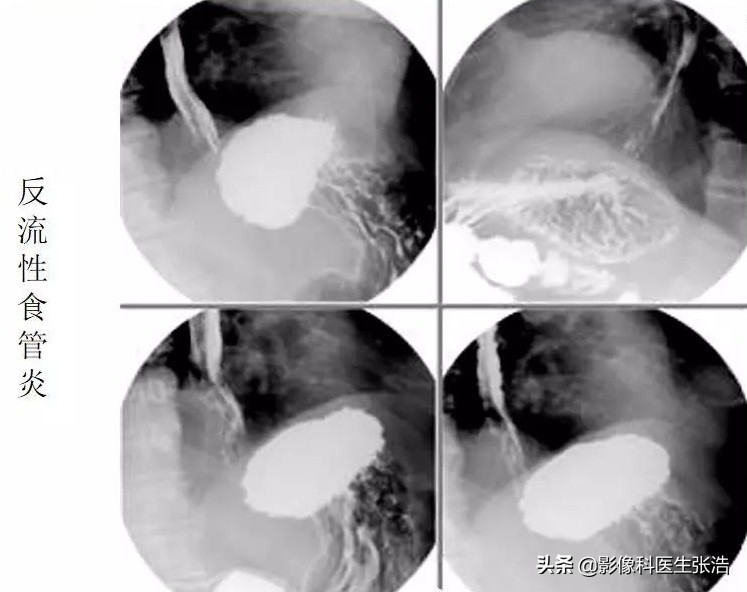

一、 反流性 食管炎:也就是大家常说的胃反酸

在饭后,时不时的感觉到有胃酸反流,然后就会觉得整个食管火辣辣的,反流性食管炎发生是因为食管下端括约肌功能失调,胃和(或)十二指肠内容物反流入食管,引起食管粘膜炎症,患者常常会有一种“烧心”的感觉。特别是在餐后会出现胸骨后烧灼痛,心绞痛样疼痛,反酸,曖气,甚至吞咽困难和少量呕血。

因为反流的胃酸对食道黏膜具有一定的损伤,所以急性期为粘膜充血、水肿,易出血,形成糜烂和表浅溃疡。

上图就是典型的反流性食管炎的钡餐图像,可以看看到局部食道粘膜毛躁,特别是接近胃部入口处(贲门部),长期受到反流的胃酸刺激所致。